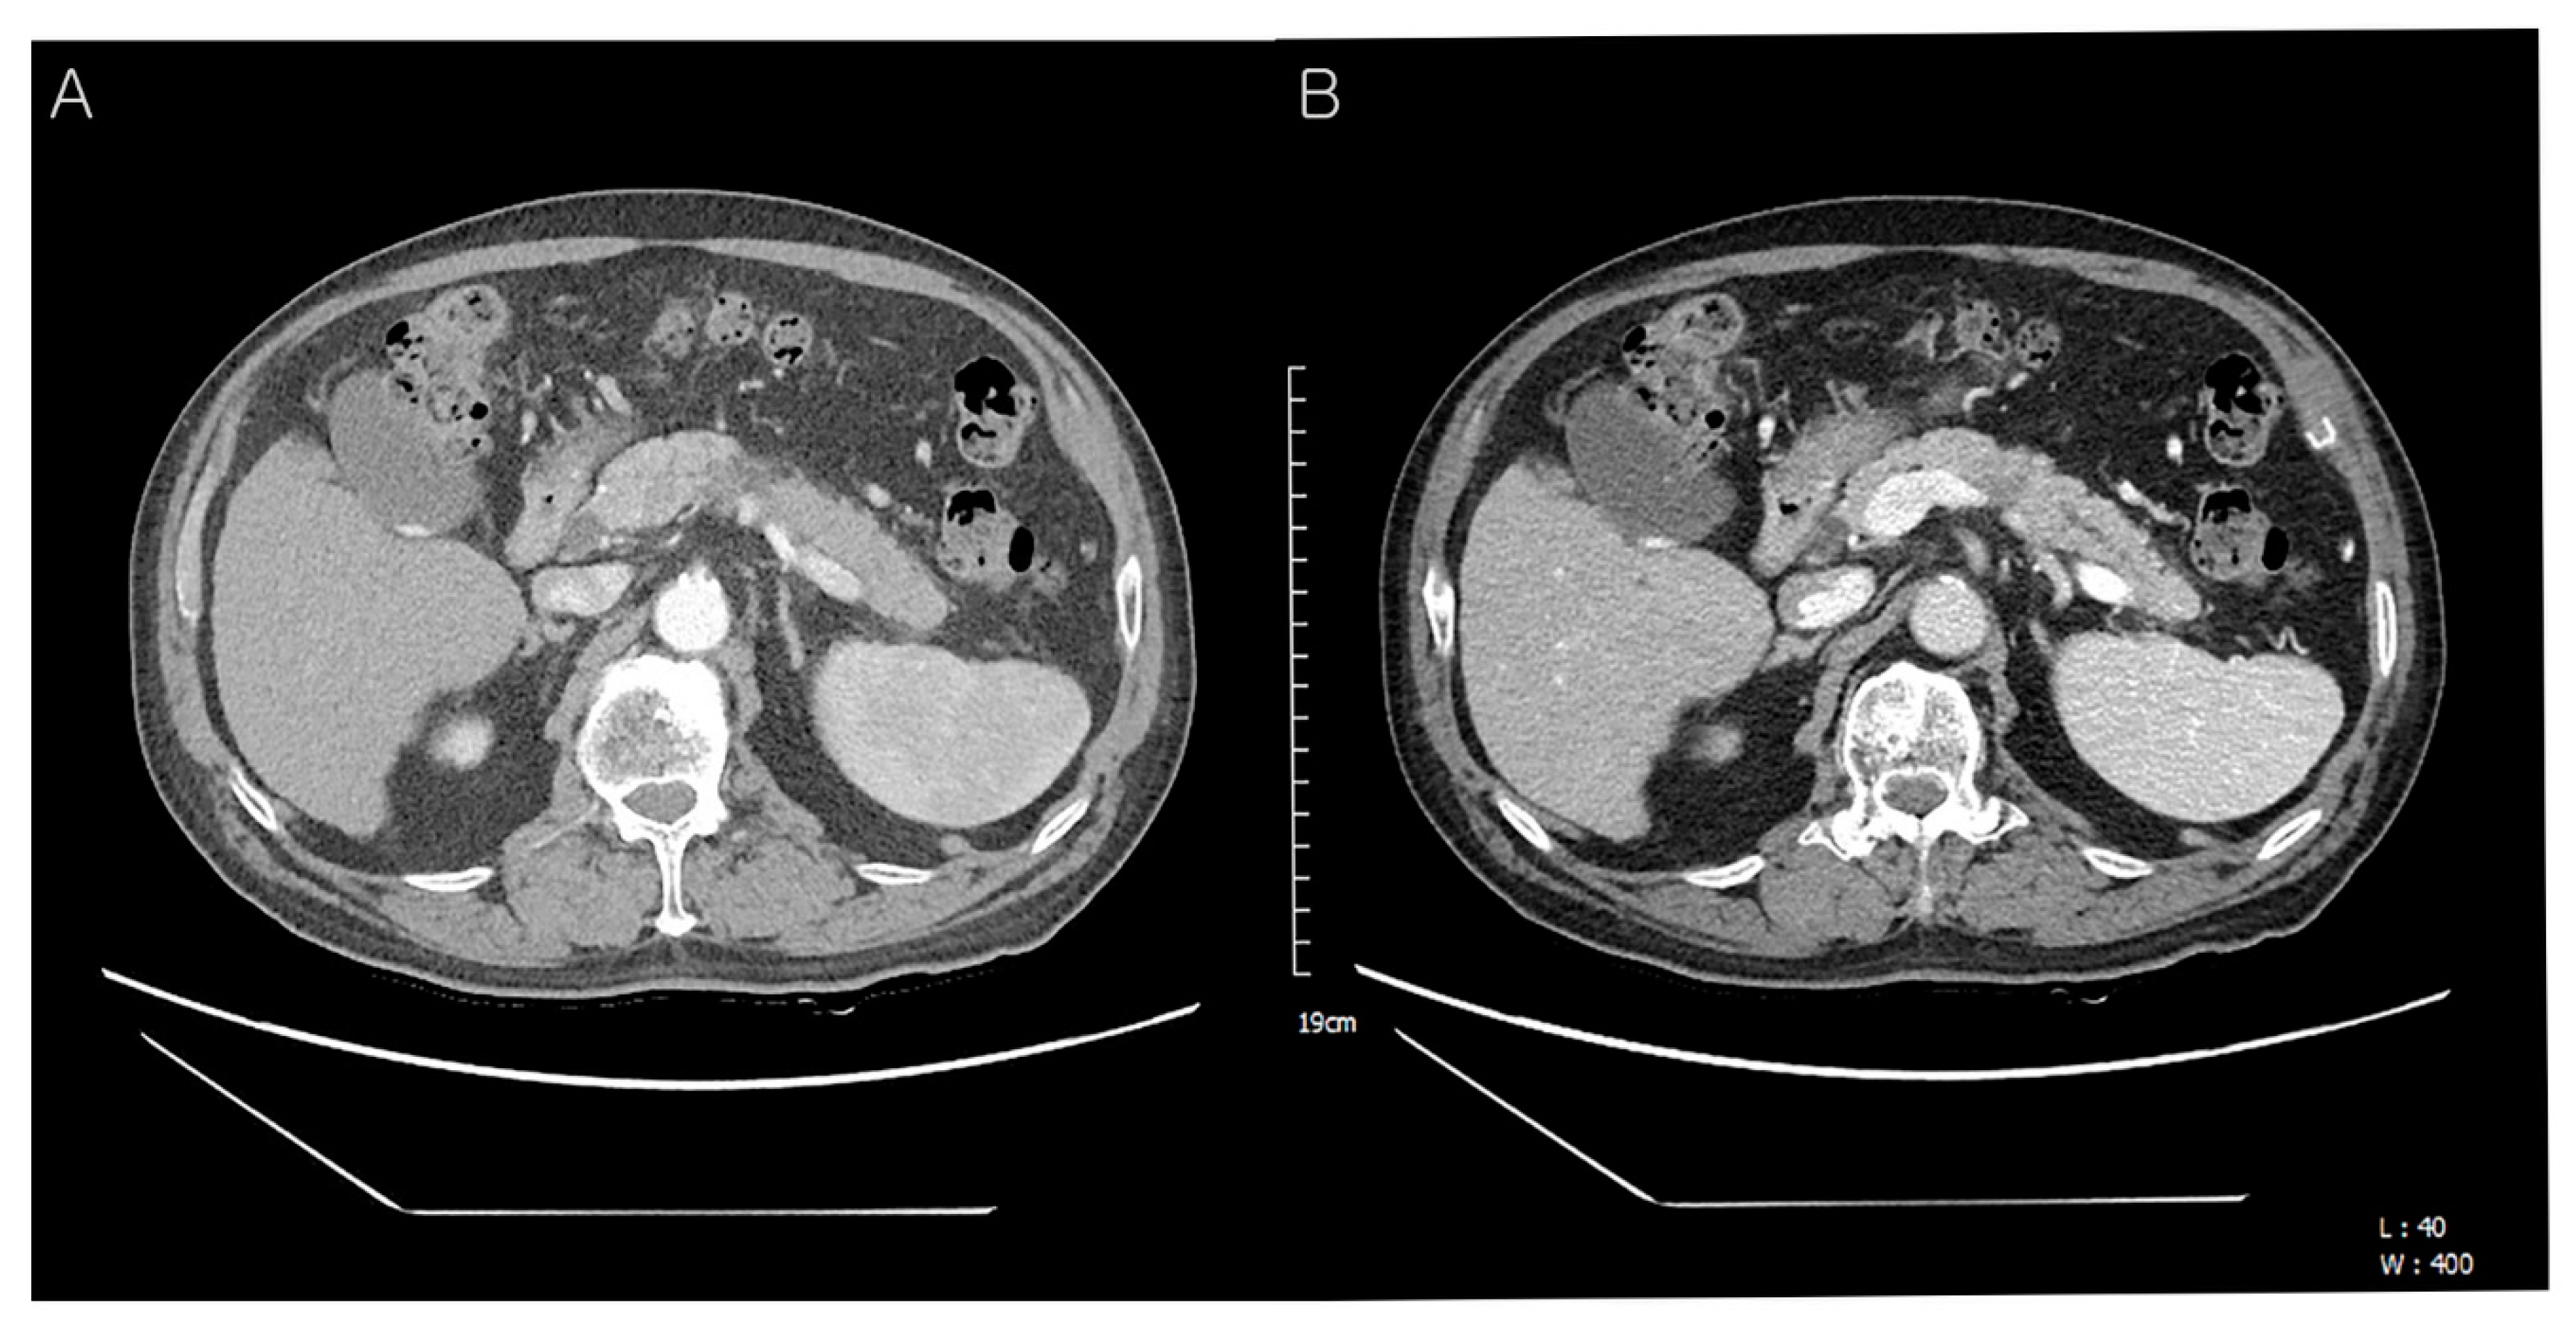

Preoperative abdominal computed tomography (CT) findings. A 72-year-old man presented with a pancreatic mass on abdominal CT. However, he had no other symptoms of jaundice, abdominal pain, or weight loss. On physical examination, the liver and spleen were not enlarged and the vital signs were stable. He was diagnosed with hepatitis B and C 30 and 10 years ago and had received anti-viral treatment (Table 1). Subsequently, he was diagnosed with hepatocellular carcinoma in segment 7 and treated with radiofrequency ablation (RFA). Eight years later, an additional RFA treatment was performed for the newly developed hepatic mass in segment 8 (Table 1). The laboratory data were as follows: total protein 6.7 g/dL (normal: 6.6–8.7 g/dL), albumin 4.0 g/dL (normal: 3.5–5.2 g/dL), total bilirubin 0.37 mg/dL (normal: <1.2 mg/dL), direct bilirubin 0.2 mg/dL (normal: 0.01–0.3 mg/dL), serum AST 17 U/L (normal: ≤40 U/L), ALT 19 U/L (normal: ≤41 U/L), serum CEA 2.3 ng/mL (normal: 0–7.0 ng/mL), serum CA19-9 121.0 U/mL (normal: 0–37.0 U/mL), amylase 98 U/L (normal: 28–110 U/L), lipase 91 U/L (13–60 U/L), BUN 16.3 mg/dL (normal: 6–20 mg/dL), creatinine 0.58 mg/dL (normal: 0.7–1.2 mg/dL). Follow-up contrast-enhanced abdominal CT showed an approx. 4.0 cm-sized hypodense mass in the distal body and tail of the pancreas with an irregular margin (A). The upstream pancreatic duct dilatation was also detected (B). Hence, the patient’s condition was diagnosed as pancreatic ductal adenocarcinoma preoperatively.